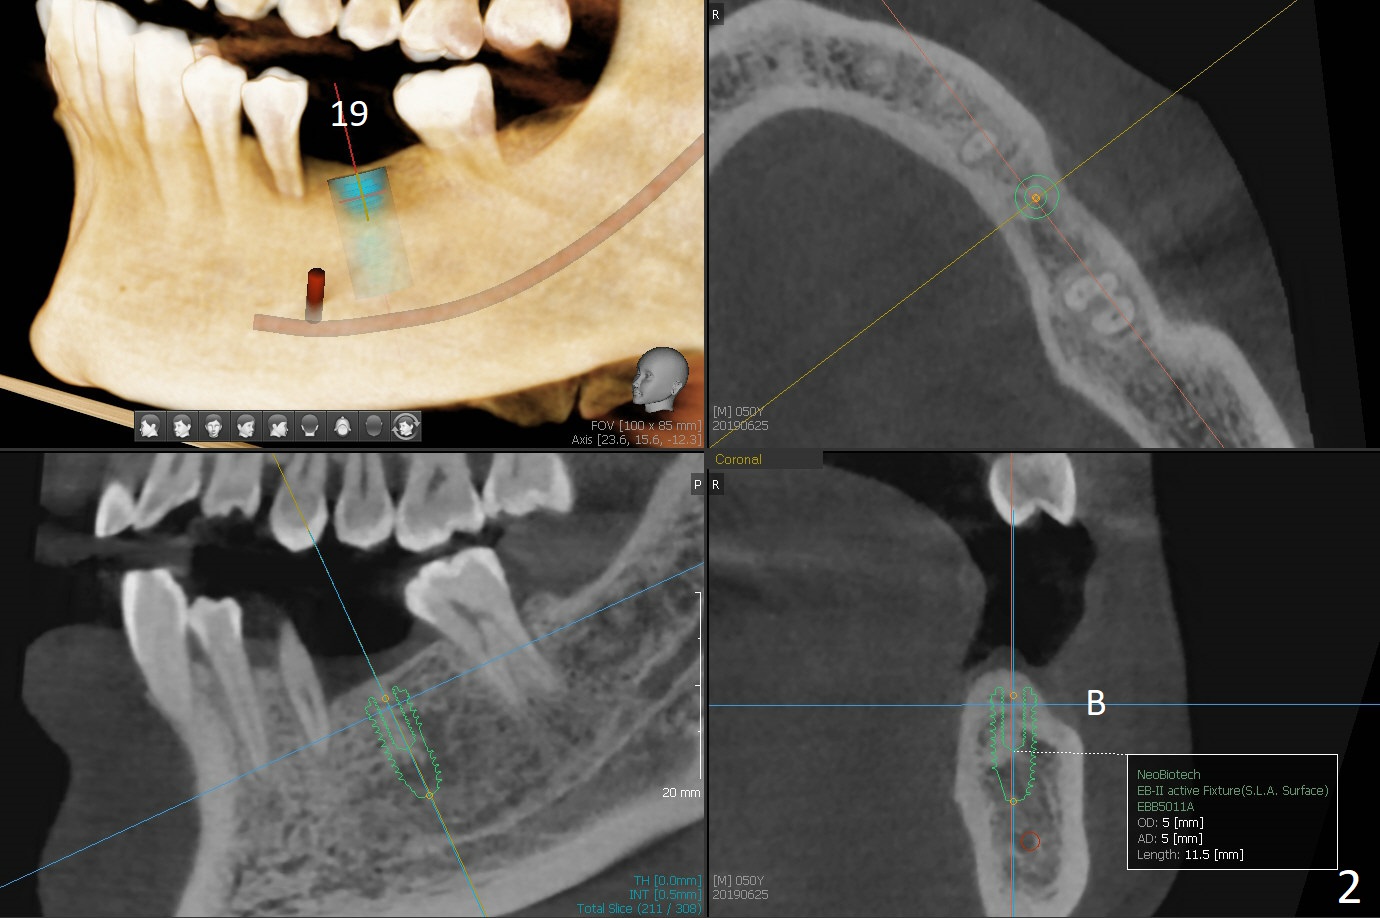

A 50-year-old man loves chewing bone and crab leg. The tooth #19 was extracted due to fracture 1.5 years ago (Fig.1). To reduce abutment screw loosening, IS guide will be used to create osteotomy, while a Tatum implant will be place initially with the guide (Fig.2). There appears no screw loosening associated with Tatum implants. The ridge at #8 is atrophic; a 2.5x10 mm Mini-implant will be placed palatal (Fig.3). The mesiopalatal defect (Fig.4 (lingual view) *) will be bone grafted after implant placement. Incision will be made after the 1st drill for access. The guide will be made with gingival clearance. A piece of 6-month membrane will be cut with a hole buccally to cover the bone graft and slide through the implant.